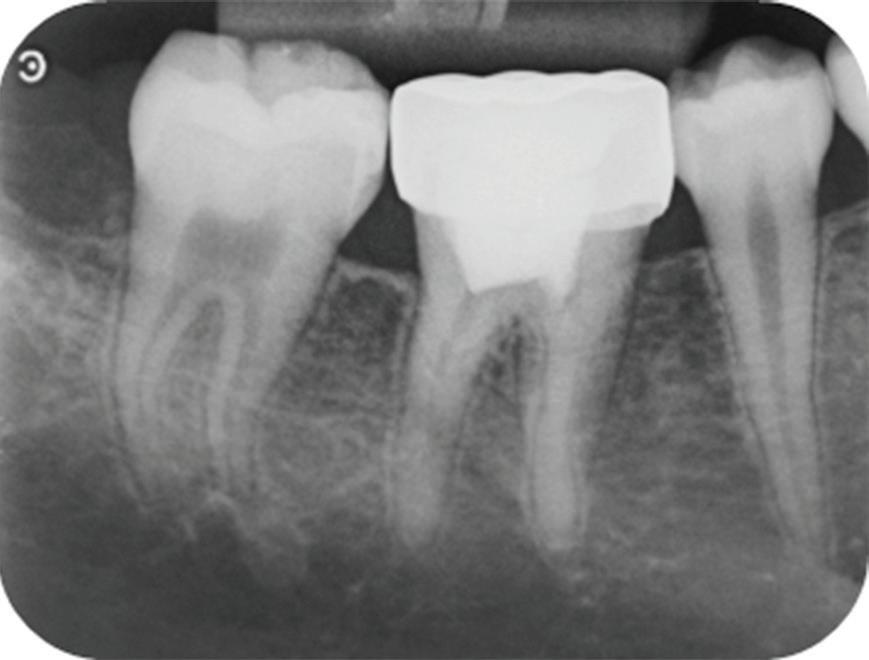

Fig 7. Periapical radiograph 6 months after placement of a stainless steel crown, showing possible widening of the periodontal ligament space.

Fig 8.

Radiograph 15 months after stainless steel crown placement, showing periapical radiolucency that indicates vital pulp therapy failure 49 months after partial pulpotomy.